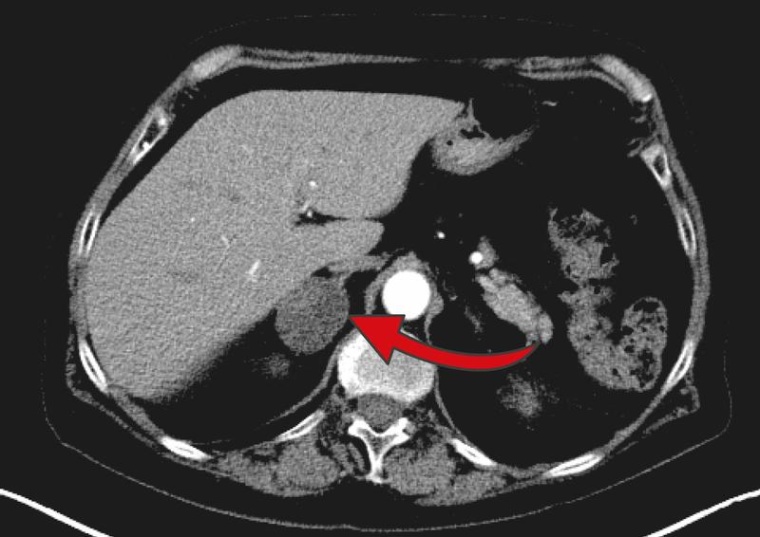

Denn drei Prozent der über 50-Jährigen und zehn Prozent der über 80-Jährigen haben Nebennieren-Zufallstumore, auch Nebennieren-Inzidentalom genannt. Diese Tumoren werden per Definition zufällig bei einer bildgebenden Untersuchung des Bauchraums entdeckt, zum Beispiel bei Gallenbeschwerden, Verdacht auf Nierensteine oder Rückenschmerzen. Weniger als zehn Prozent dieser Nebennieren-Zufallstumore sind bösartig, weitere zehn Prozent führen zu einem starken Hormonüberschuss, die restlichen 80 Prozent wurden lange Zeit zur Gruppe der klinisch hormoninaktiven Tumoren gezählt. „Schon länger war allerdings bekannt, dass fast jeder Zweite aus dieser Gruppe eine leicht erhöhte Produktion des Hormons Kortisol aufweist. Ob dieser leichte Kortisolüberschuss krank macht, war unklar“, berichtet Martin Fassnacht. Der Endokrinologe schätzt, dass circa eine halbe Million Bundesbürgerinnen und Bundesbürger betroffen sein dürften.

Dennoch blieb unklar, ob der Tumor operativ entfernt werden soll oder nicht? Prof. Antoine Tabarin, Leiter der Endokrinologie am Universitätsklinikum Bordeaux in Frankreich, initiierte deshalb die Interventionsstudie CHIRACIC, in der die Auswirkungen der chirurgischen Entfernung des Inzidentaloms auf den Blutdruck untersucht wurde.